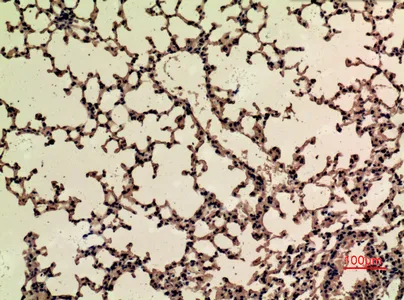

CD68 Rabbit Polyclonal Antibody

Cat: APRab08436

Size1:50μl Price1:$118

Size2:100μl Price2:$220

Size3:500μl Price3:$980